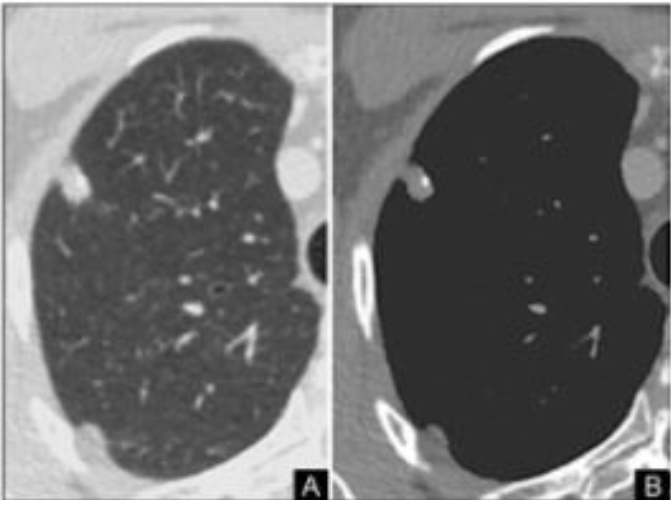

NÓDULO SOLITÁRIO

MELHOR MODO DE VERIFICIAR MALIGINIDADE É VER O CRESCIMENTO NOS ULTIMOS DOIS ANOS

PRESENÇA DE LESÃO PERIFÉRICA, AQUAL , É REALIZADA BX COM VIDEOTORACOSCOPIA.